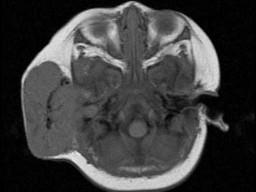

问题 老年患者,右侧面部肿胀,呈青紫色,MRI检查如图所示,请选择最可能的诊断 ( )

选项 A、神经纤维瘤 B、神经鞘瘤 C、囊肿 D、脓肿 E、血管瘤

答案 E